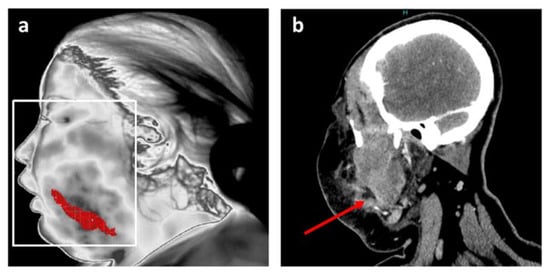

| Additional radiological examination | CT scan of face and neck | Cone Beam CT |